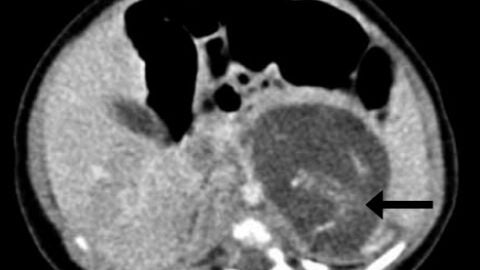

Cada “feto” tenía cuatro extremidades, piel, una caja torácica, los intestinos y un tejido cerebral primitivo. Ambos estaban unidos por un cordón umbilical, según describen los especialistas que atendieron atónitos al parto, que tuvo lugar en 2010.

El estado de desarrollo de los fetos (o tumores) podría situarse entre las ocho y diez semanas de gestación, según los expertos. Tenían espinas dorsales, genitales externos ambiguos y aún no habían desarrollado el cráneo.

La teoría habitual para estos casos es que los fetos adicionales se desarrollan desde el principio del embarazo, para luego ser absorbidos por el principal, dejando de crecer. Pero aquí las dos masas con tejido no se descubrieron hasta las 37 semanas, teniendo las dos un idéntico nivel de desarrollo de órganos.